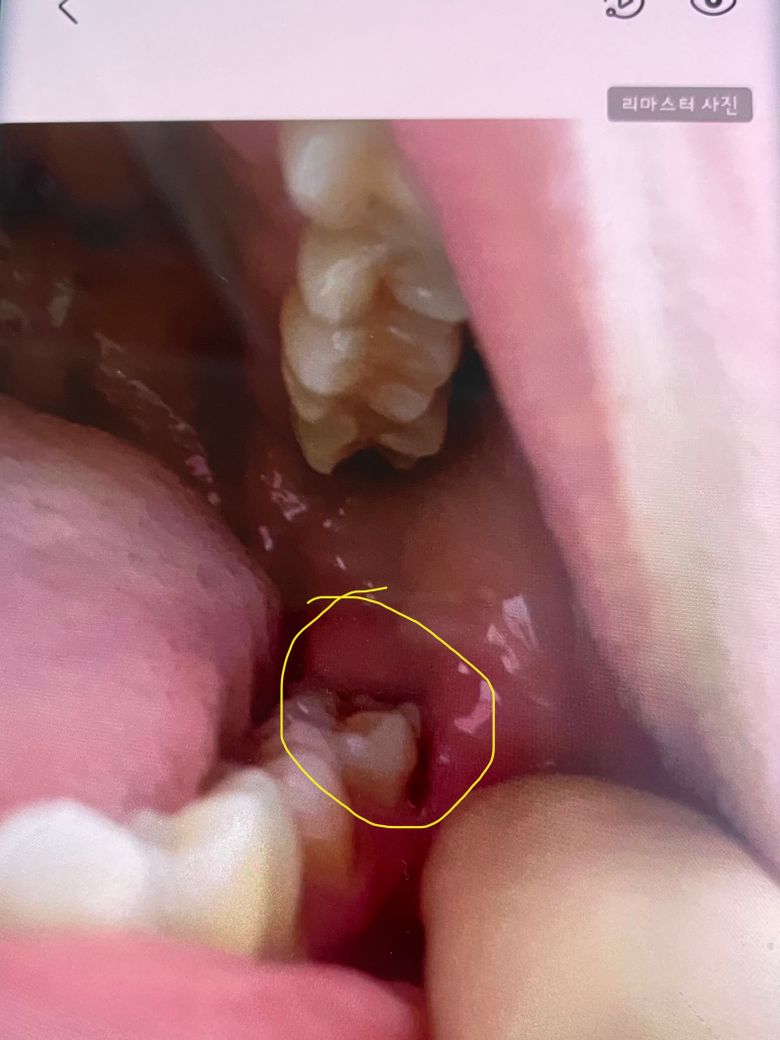

어금니 바깥쪽 충치인가요? 치석인가요?

사진상으론 까맣게 보이는데

실제론 갈색입니다.

저 어금니 씹는면에도 실 충치 2개 작게 있어요.

충치라면 레진으론 안되겠죠?ㅠㅠ

저쪽 어금니 찬거 먹으면 시린 지는 꽤 됐어요.

• 1번 째 사진

사진만으론 명확히 보이진 않습니다. 충치가 있어보이진 않지만 의심되면 치과를 가보시는 게 좋겠습니다.

갈색이라면 치아가 선천적으로 약하게 태어나서 그럴수도 잇고 예전에 치료햇던거 착색되서 그럴가능성도 있습니다.

일단 지금 사진으로는 잘 보이지 않습니다. 정확한 평가를 위해서는 더 선명한 사진이 필요합니다. 현재 너무 걱정이 되신다면 다시 치과를 방문하여 해당 부분에 대한 검사를 해보는 것이 가장 좋아 보입니다.

해당 부위는 충치가 잘 생기지는 않습니다. 사진상 정확히 보이지는 않으나 충치보다는 치석, 치태의 가능성이 높아보입니다.